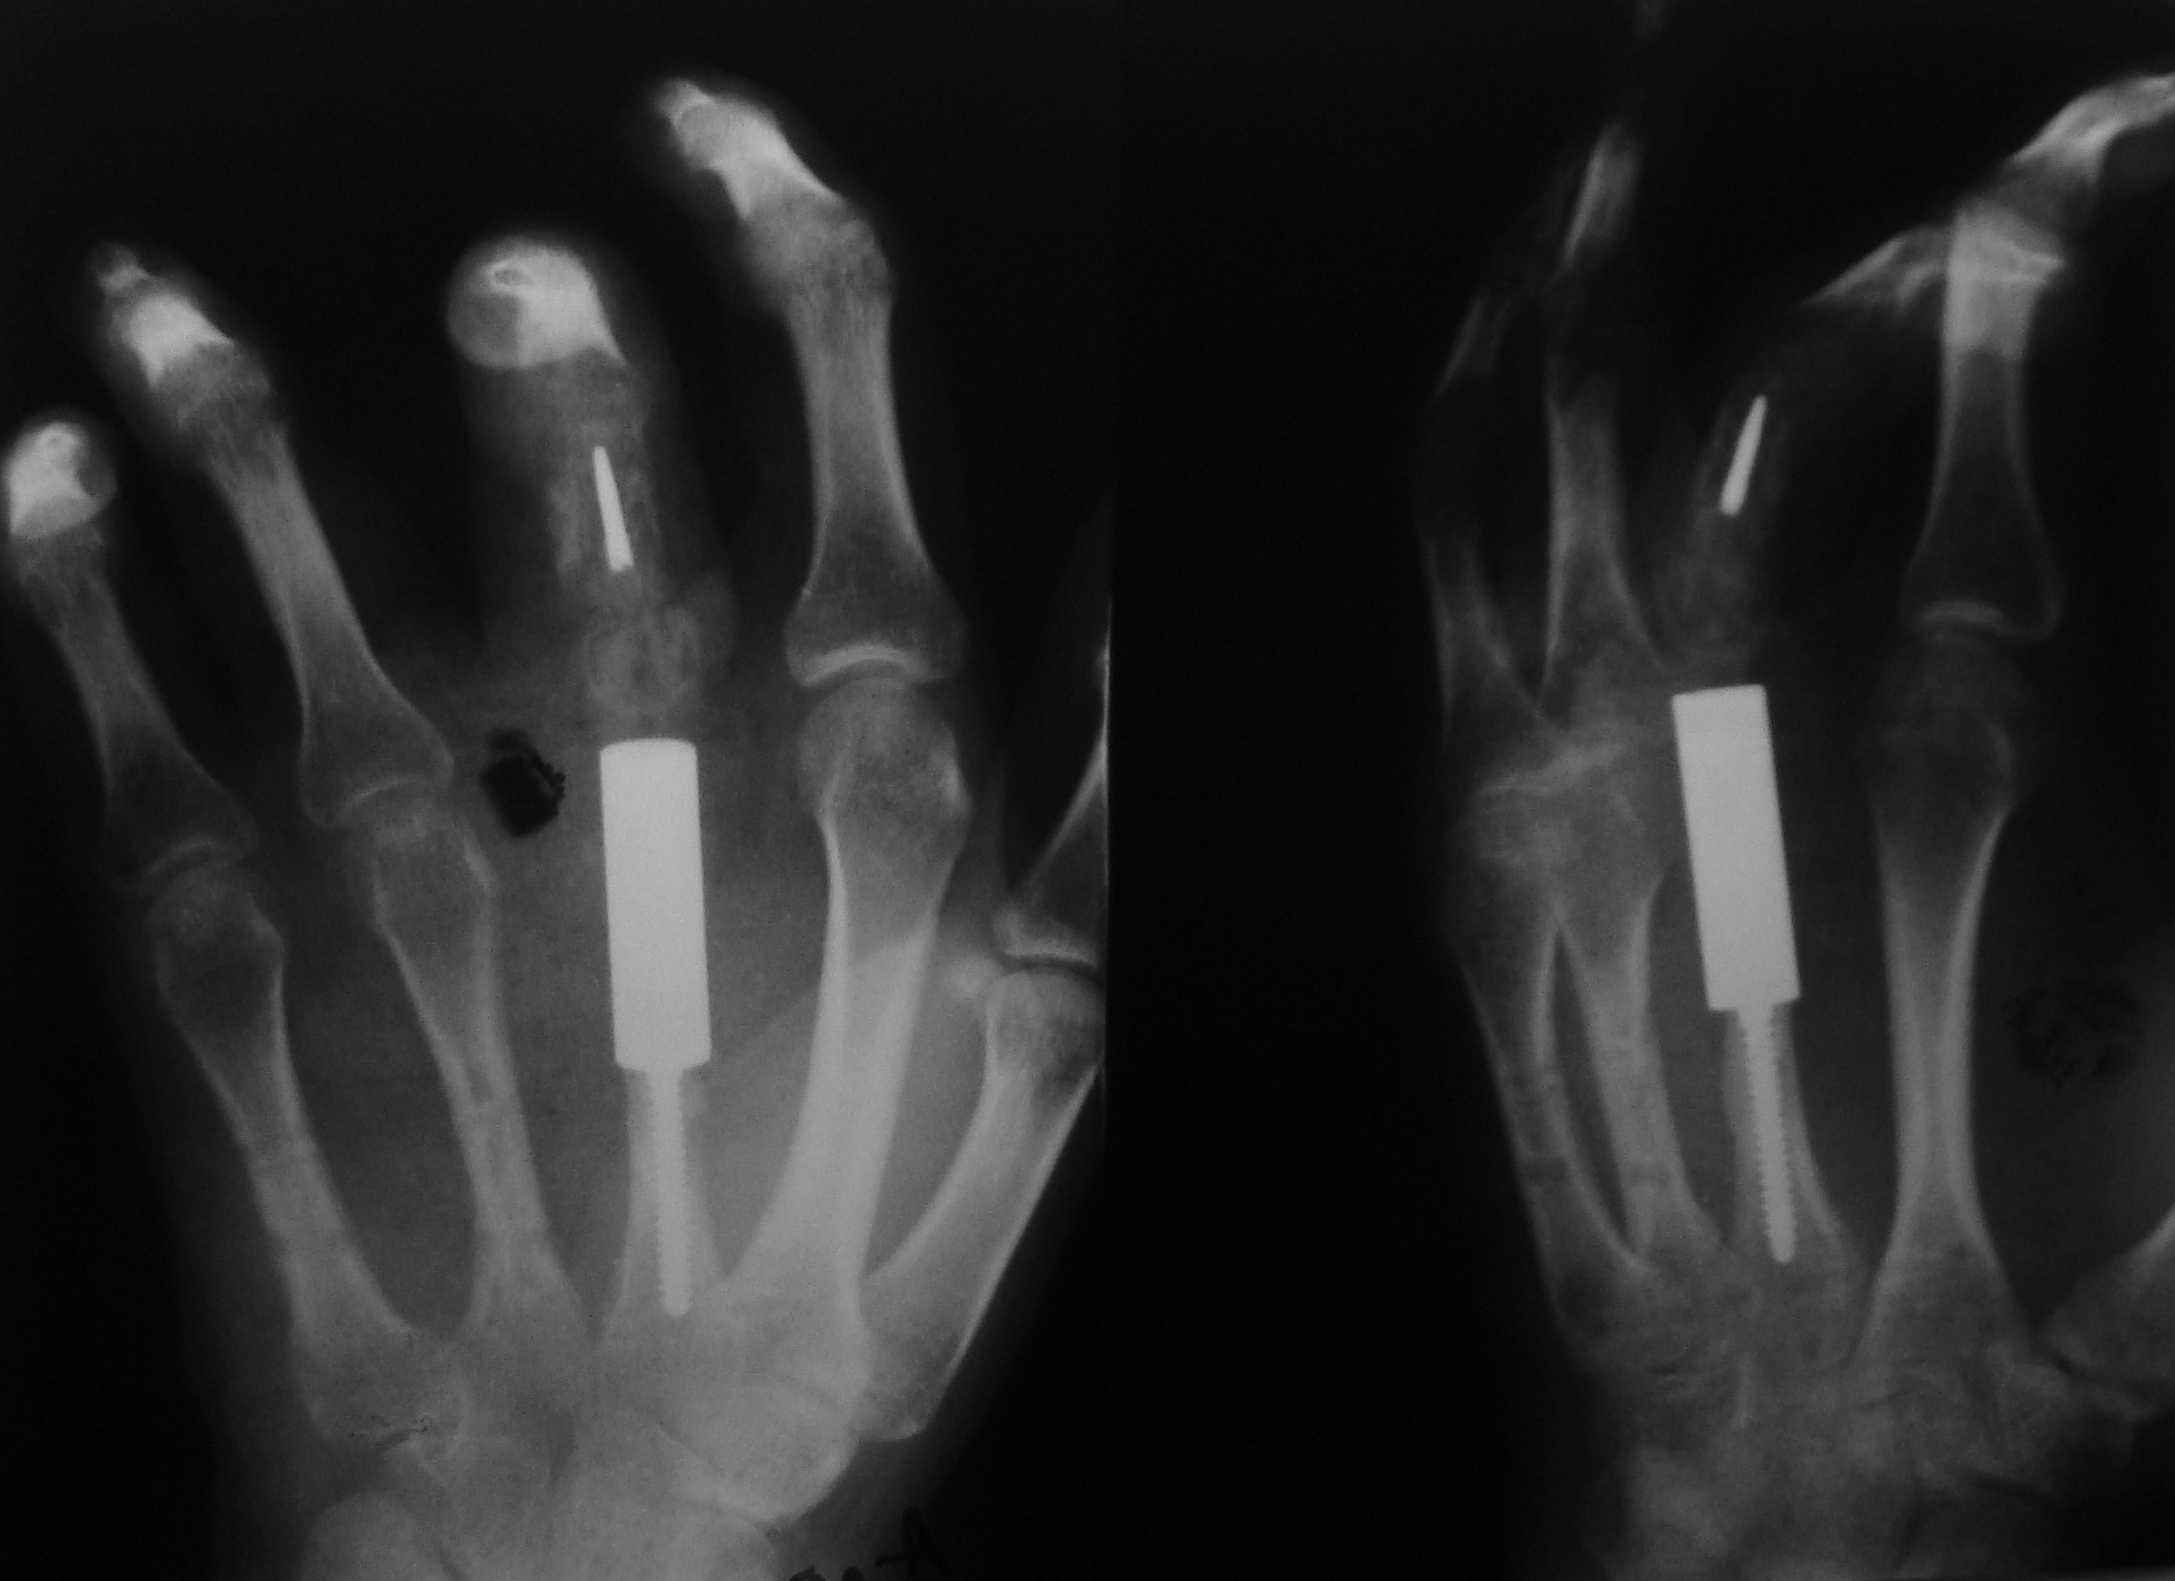

Согласен с глубокоуважаемым Игорем Владимировичем в вопросе выбора оптимального трансплантат для замещения пострезекционного дефекта 2-й пястной кости, если речь идет о васкуляризированной костной пластике. У нас есть опыт замещения посттравматических дефектов пястных костей титановым протезом пястной кости (к сожалению пока самодельным)в сочетании с одномоментным эндопротезированием пястно-фалангового сустава протезом фирмы Синтез. Рентгенограммы обнародую завтра.

обещанные снимки